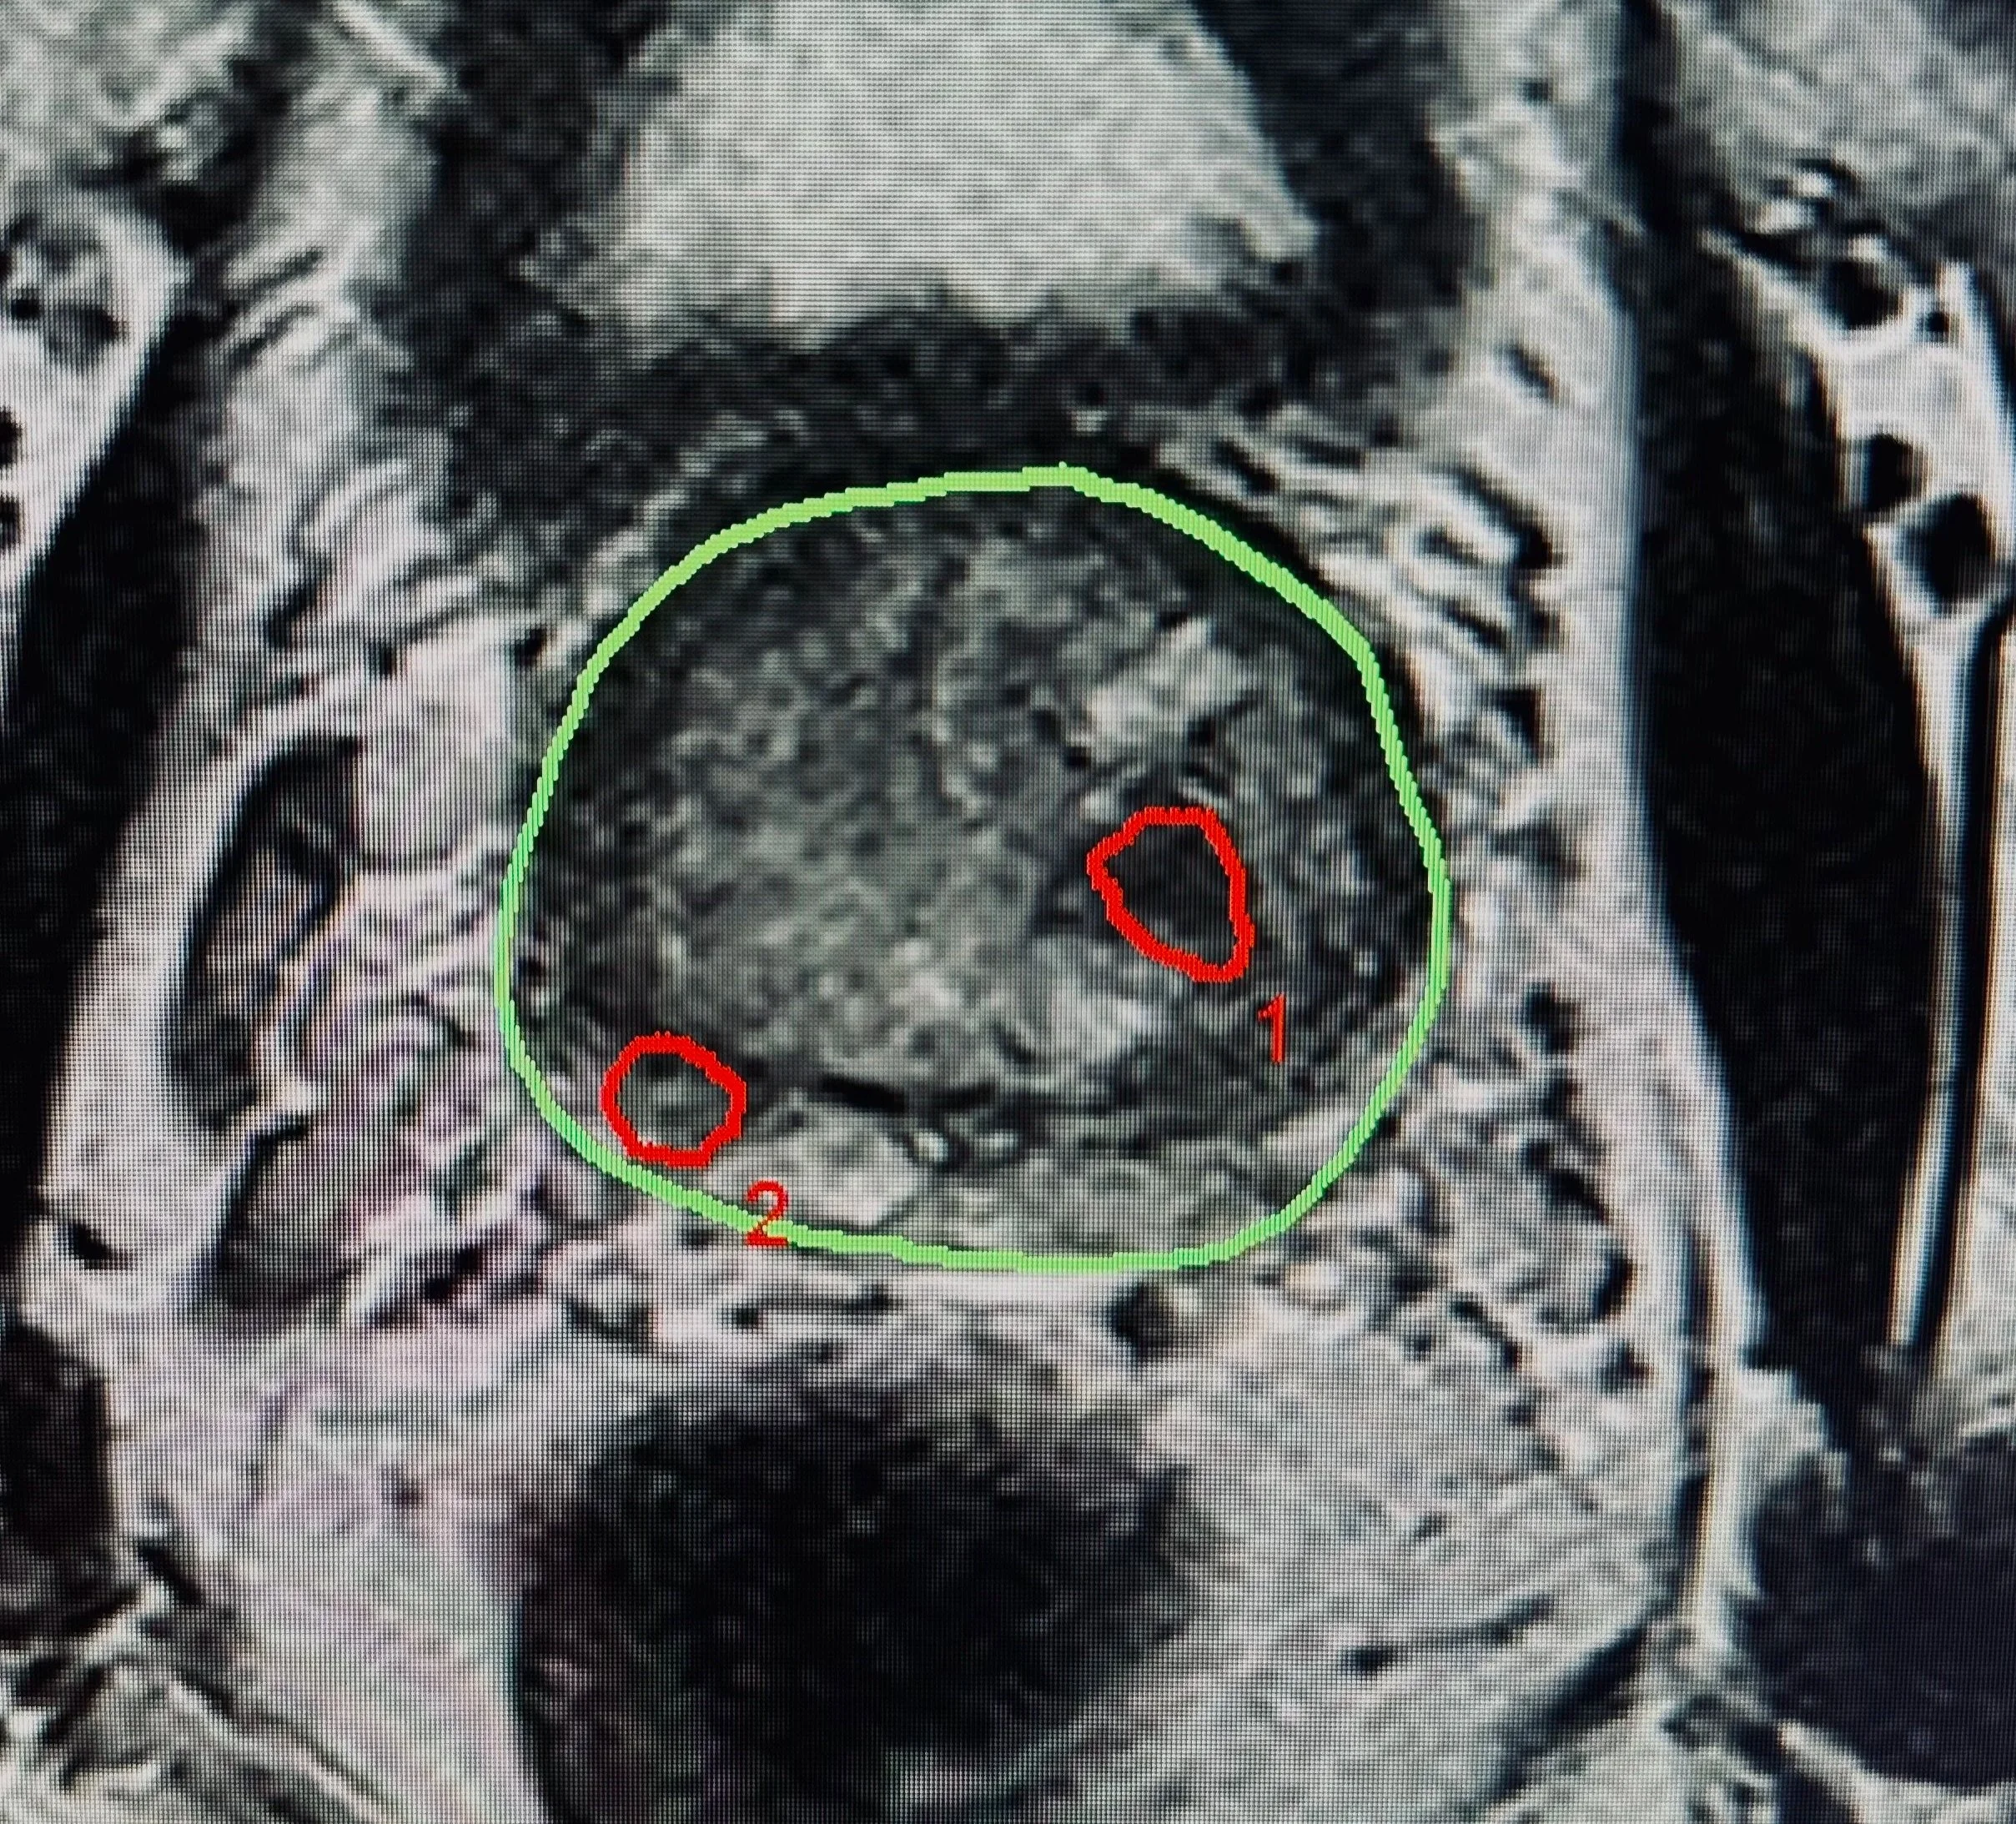

Durch das Artemis System können auch kleinste suspekte Krebsherde zielsicher biopsiert werden. Unser Artemis System ist das erste dieser Art in Österreich und eines von wenigen in Europa.

Mit dem Artemis TP System können selbst kleinste MRT-Herde angesteuert und zielsicher biopsiert werden. Ein ergänzendes Protokoll bietet optimale Bedingungen für eine Kontrollbiopsie oder OP-Planung.